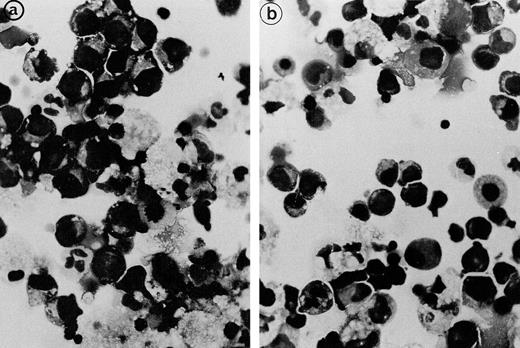

The erythroblastic synartesis could be reproduced in vitro: indeed, erythroblast cultures established with bone marrow progenitors from cases 2 and 3 displayed similar morphological abnormalities to those observed in vivo (Fig4a, see page 3686). Crossed culture experiments using the patient erythroblasts grown in the presence of their own serum or of a control serum, or using erythroblasts of a control subject grown in the presence of the patient sera (see Table1) were performed and gave the following results: the erythroblast abnormalities reproduced in culture in the presence of autologous serum were absent when the culture was performed with a control AB serum (Fig 4b). Electron microscopy confirmed these findings, showing that the same intercellular junctions were observed when the patient erythroblastic progenitors were cultured with autologous serum, but that they were absent when the culture was performed in the presence of a control serum. These abnormalities were not reproduced in vitro when the erythroblasts were grown in the patient sera that had been IgG depleted. This allowed us to conclude that the synartesis was caused by an IgG component. Further confirmation was given by the observation that cultured normal erythroblasts displayed authentic synartesis when grown in the presence of patient to serum. Finally, the IgG fractions from the patients were added to normal serum at a concentration of 2 g/L and were able to induce typical synartesis on control erythroblasts grown in this preparation (Fig 5).

Light microscopical aspect of the erythroblasts cultured from patient 2 bone marrow. (a) In the presence of autologous serum: The erythroblasts are closely apposed to each other with occasional nonbasophilic areas present at their junction, mimicking the morphology of the bone marrow smears. (b) In the presence of a control serum: The grown erythroblasts are scattered and individually disposed on this cytospun preparation and do not display the characteristic abnormalities of the disease.